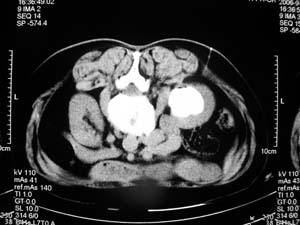

图像太少,没有见到硬化剂,肾囊肿治疗为安全起见应常规造影.

我们主要在ct引导下进行各种囊肿的穿刺引流,对于肾囊肿治疗的较多.穿刺成功后尽量抽尽囊液并且记录数量,抽尽后注入造影剂看看是否与尿路相通,然后用1/4的比例注入无水酒精进行硬化.跟踪观察治愈率达98%以上.